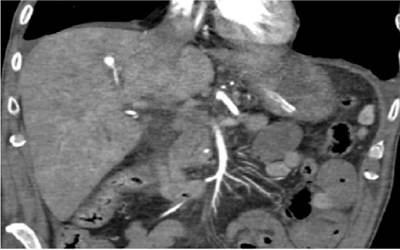

A partir de estos hallazgos, se realizó una angiotomografía computarizada (angio-TAC) (Figura 1), que permitió objetivar el aneurisma de una rama segmentaria de la arteria hepática derecha, con contenido fusiforme sugerente de hematoma intraluminar biliar.